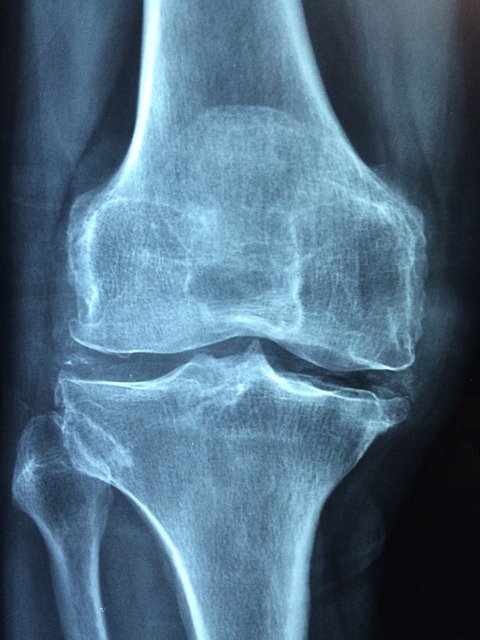

L’arthrose

FICHE L’Arthrose L’arthrose ou rhumatisme chronique est une affection dégénérative des articulations. C’est une maladie de la cinquantaine, mais beaucoup… Read More

La coxarthrose

FICHE La coxarthrose C’est le rhumatisme chronique de la hanche Symptômes : douleurs et impotence fonctionnelle progressive QU’EN EST-IL ?… Read More